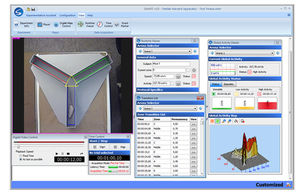

software con sistema de seguimientoSMART 3.0

Smart 3.0, la última versión del sistema de video-tracking SMART lo hace todavía más flexible e intuitivo dentro del contexto de su uso para la evaluación automatizada de la conducta en una gran variedad de aplicaciones pre-clínicas y ...